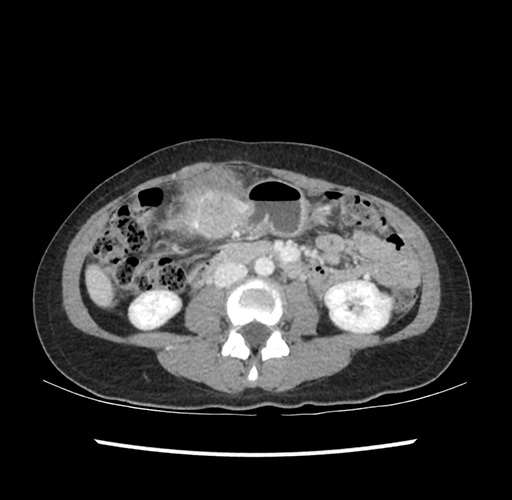

Imaging Analysis

Look through the patient's CT scan to identify any areas of concern for the necessary procedure.

Based on your CT findings, which issue(s) would give reason for "planned slowing down moment(s)" in this case?

Considering a standard left lateral sectionectomy procedure, what step(s) of the operation would you do differently in this case ?